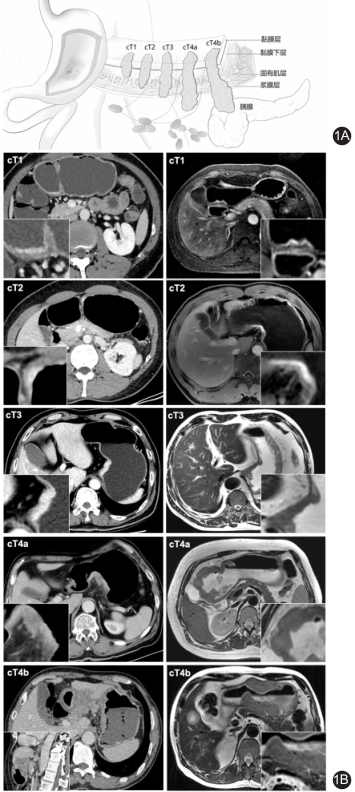

因为一般的肠型胃癌,是在胃粘膜上皮生长,胃镜进去,就一览无余,很容易发现;

而印戒细胞癌却是向胃壁外面生长,在早期,甚至在进展期,在胃粘膜表面并没有明显的改变,所以很容易漏诊。

我们的胃镜检查,就好比一个人进到屋子里观察室内的墙壁,但是壁纸下面、屋子外面的墙壁,却看不到,而这种癌就是隐藏在是墙纸下面,向外发展;

有时候取活检,由于深度不够、位置不对,都不一定能取到癌细胞。所以,临床首检漏诊率大于30%!

有必要结合超声内镜、消化道钡餐、CT等检查手段;医师取检也应该多点取检、深在取检。0Ed帝国网站管理系统